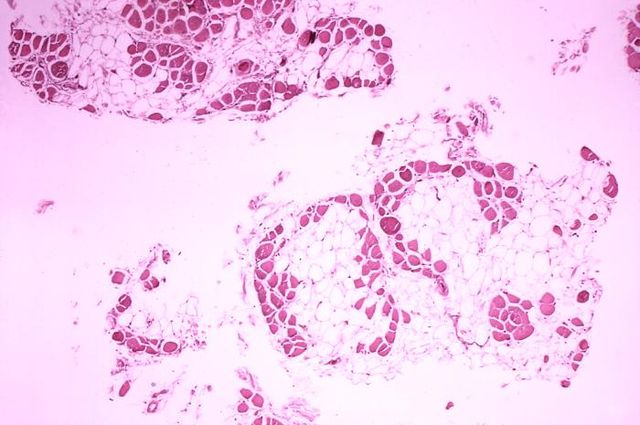

Deutsch: Histopathologisches Bild eines Querschnitts aus dem Wadenmuskel (Muskulus gastrocnemius) eines Patienten, der an Muskeldystrophie Typ Duchenne verstarb. Das Bild verdeutlicht, in welchem Ausmaß die (rot gefärbten) Muskelfasern durch Fettzellen (optisch leer = weiß) ersetzt wurden.

English: Histopathology of gastrocnemius muscle from patient who died of pseudohypertrophic muscular dystrophy, Duchenne type. Cross section of muscle shows extensive replacement of muscle fibers by adipose cells.